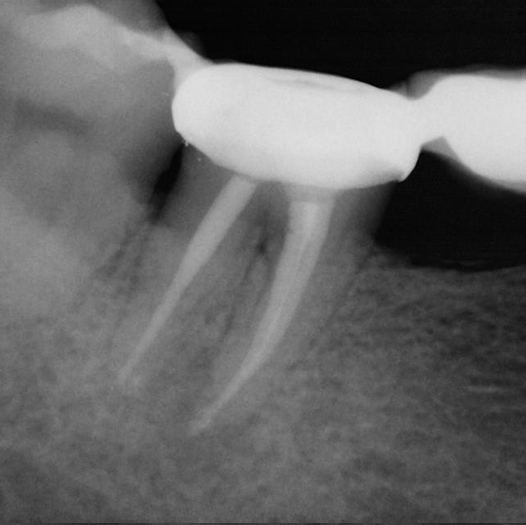

After

After Root Canal treatment